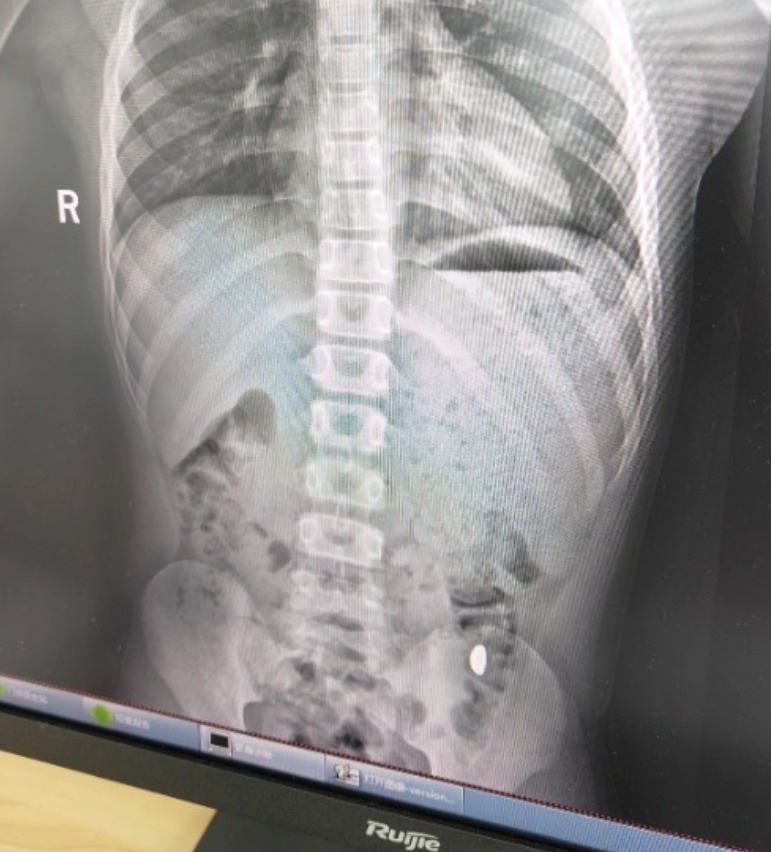

500.000 người theo dõi vụ cậu bé 11 tuổi nuốt nhầm miếng vàng 10g- Ảnh 2.

Ảnh chụp X-quang của cậu bé nghịch ngợm